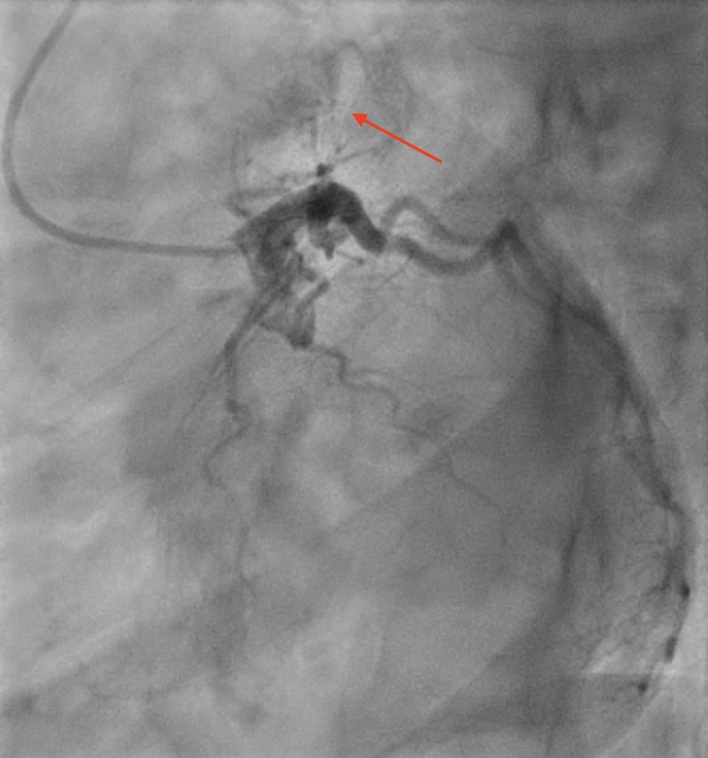

Coronary angiography showed very tortuous coronary arteries with three fistulae from the left anterior descending, left circumflex and right coronary arteries, all terminating in the pulmonary artery (figures 1–3). There was no evidence of obstructive coronary artery disease. Initial presumed diagnosis was myocardial infarction due to coronary steal syndrome. Cardiac magnetic resonance (CMR) imaging was performed. A standard protocol of white blood and cine image sequences with late gadolinium enhancement was used. Shunt assessment via formal volumetric analysis and flow analysis through the valves was performed. True forward stroke volume through the aortic valve was 99 ml/beat with a peak gradient across the valve of 8 mmHg and a regurgitant fraction of 1%. True forward flow through the pulmonary valve was 102 ml/beat. This confirmed that there was no significant shunt. Normal biventricular size and function, with no prior infarction, was also demonstrated. There was a small concentric pericardial effusion with a focal region of inferolateral epicardial fibrosis, suggesting a diagnosis of myopericarditis. The patient was treated with regular colchicine for three months, and ibuprofen, as required. Her troponin and symptoms settled and she was discharged.